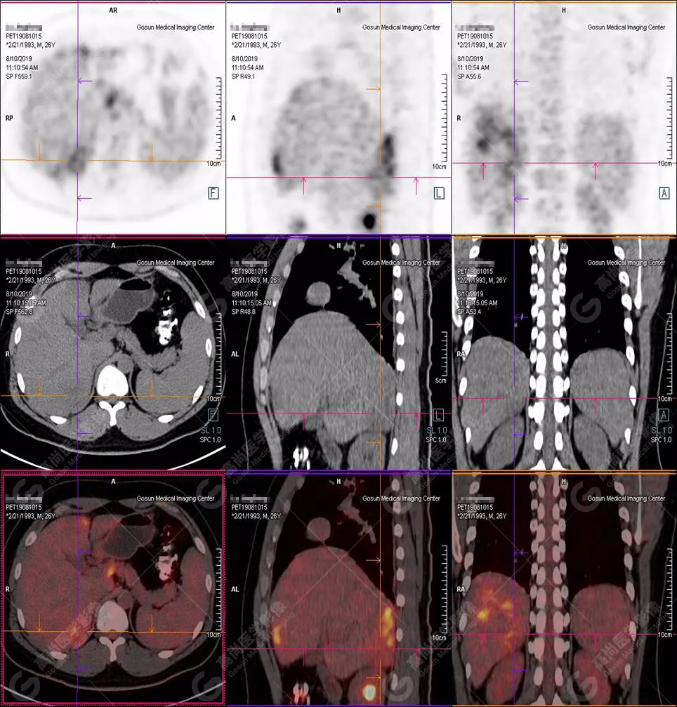

B超及CT檢查發(fā)現(xiàn):肝臟多發(fā)低密度占位。

PET/CT全身圖

PET/CT診斷

嗜酸性粒細(xì)胞增多癥肝浸潤(rùn)